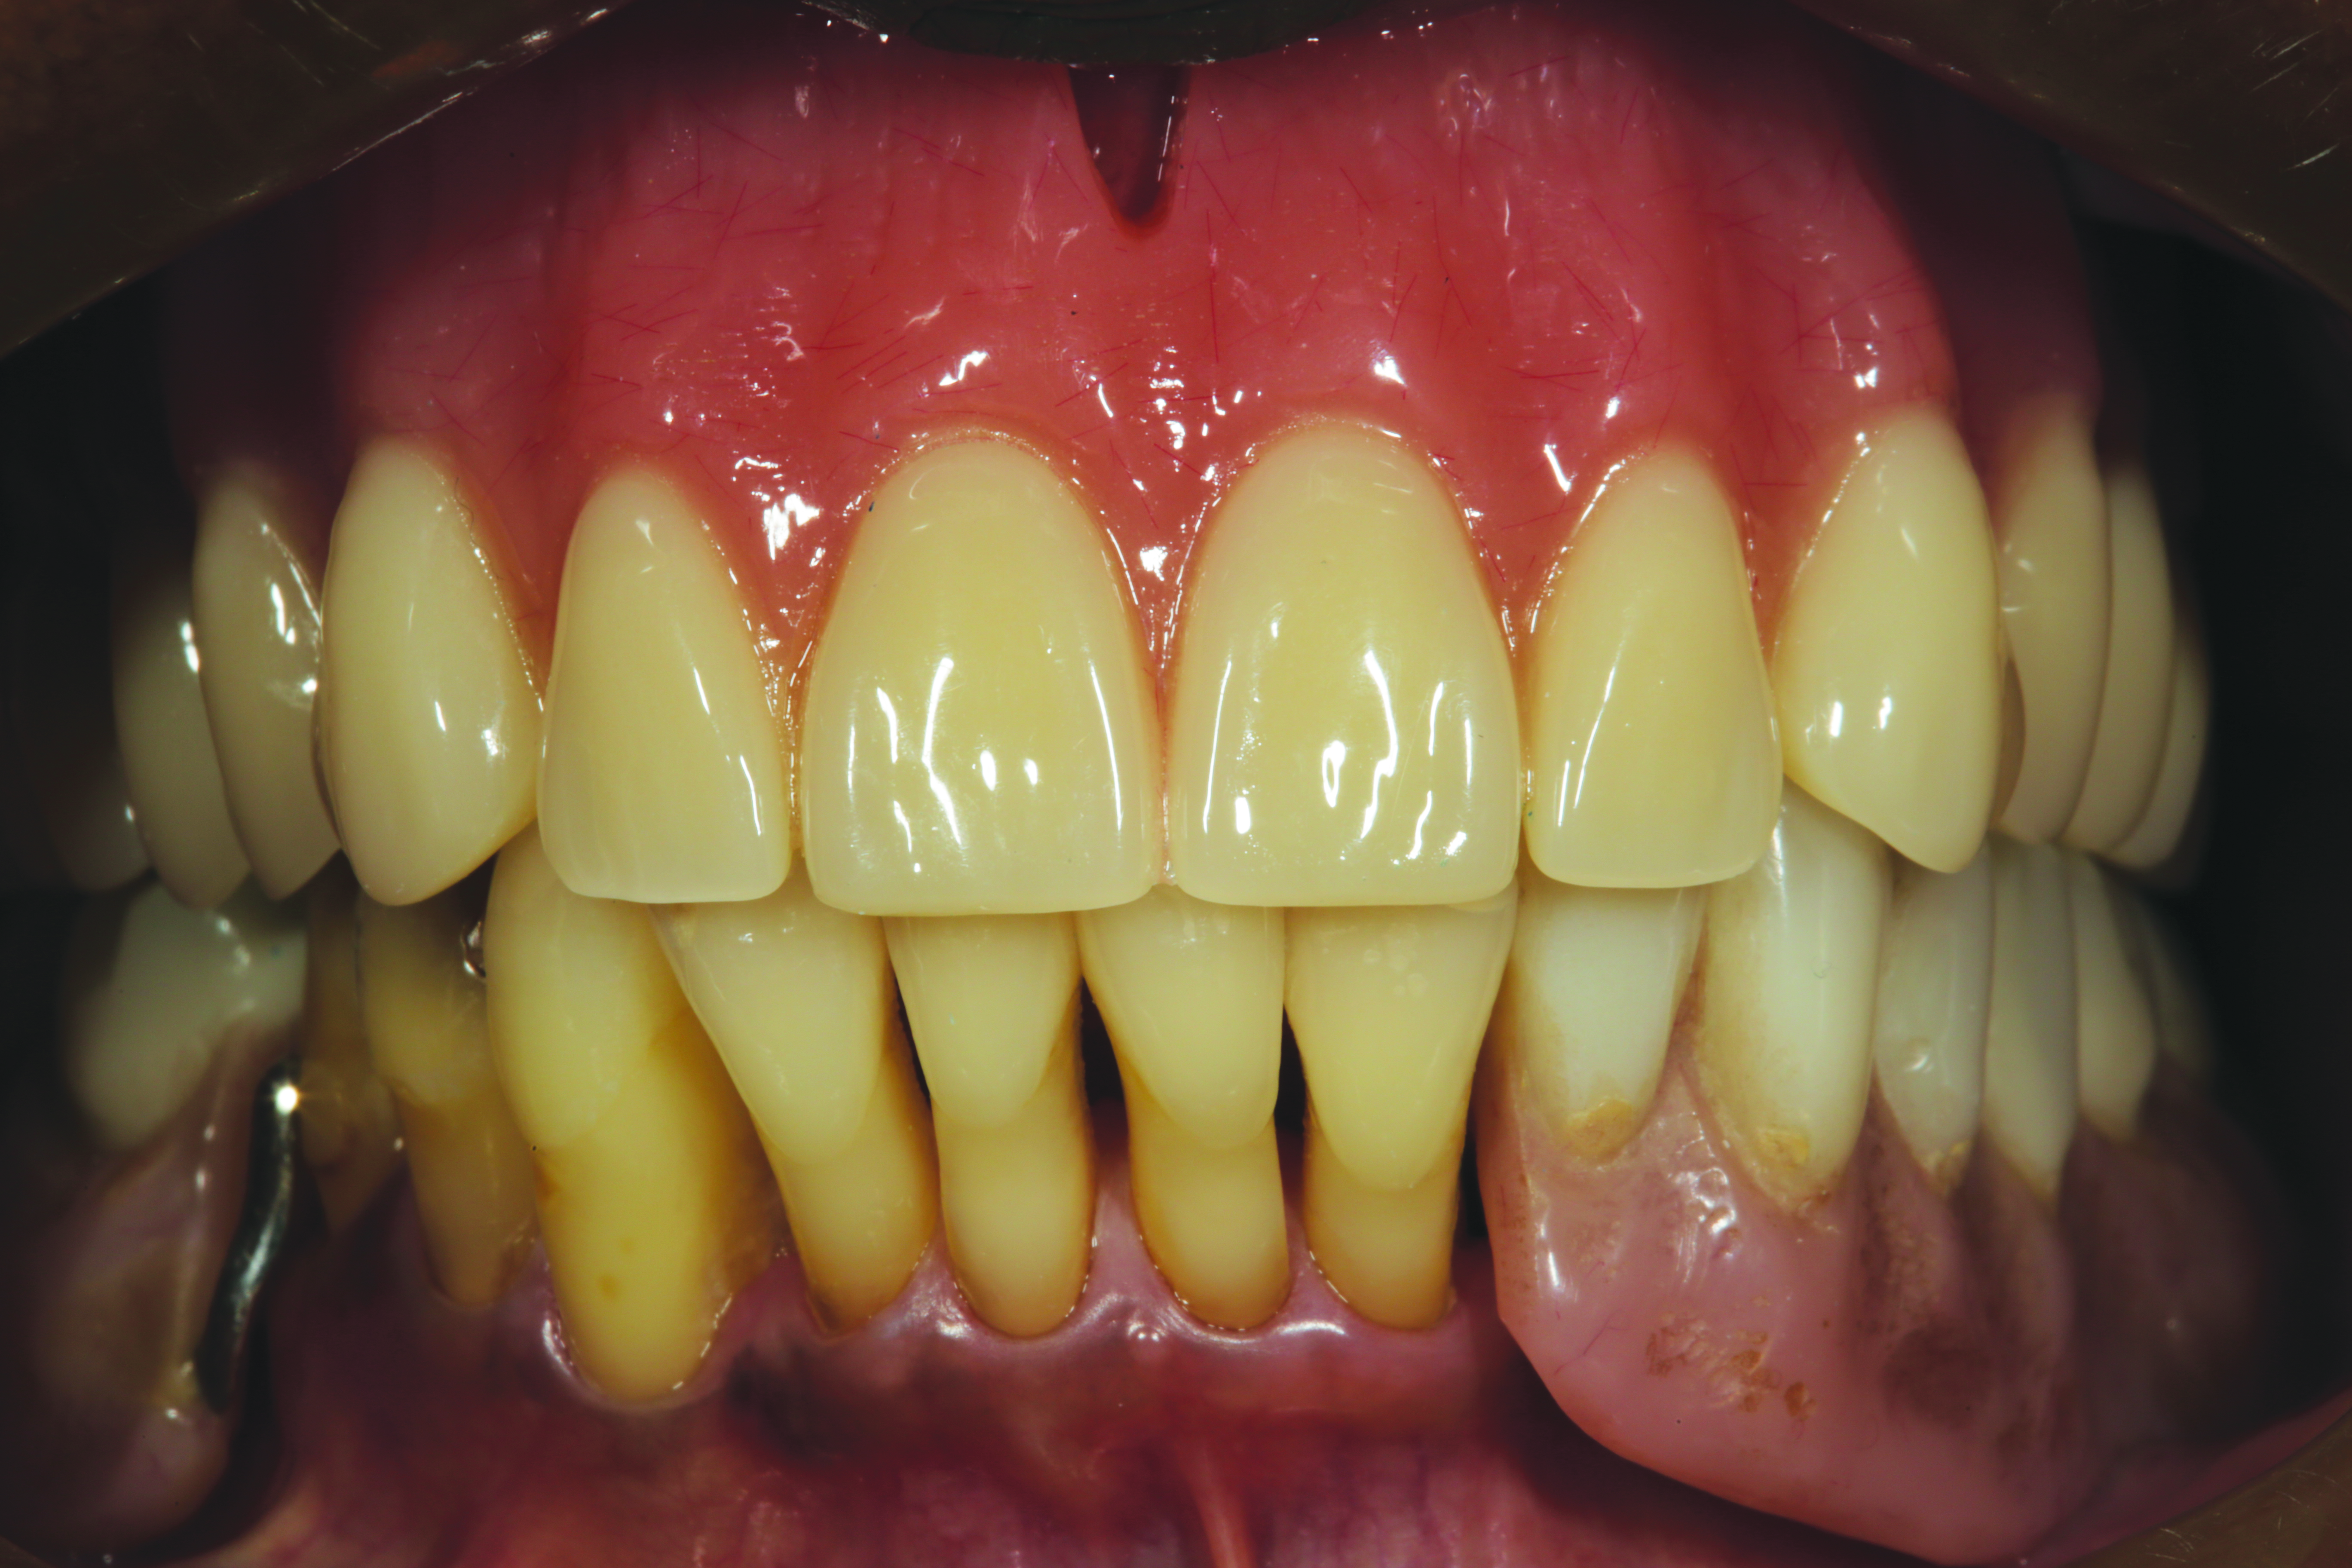

The printed try-in allowed the dentist to evaluate retention, VDO, tooth function and esthetics, phonetics, and occlusion. At this stage, any necessary changes can be noted and another try-in made if necessary. Minimal changes can be incorporated into the final prosthesis without the need for a second try-in visit (Figure 4). Retention, VDO, anterior tooth position for esthetics and phonetics, and centric occlusion were changed in this case.

Fig 4. Minimal changes can be incorporated into the final prosthesis without the need for a second try-in visit.

Figure 4